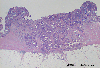

Histology